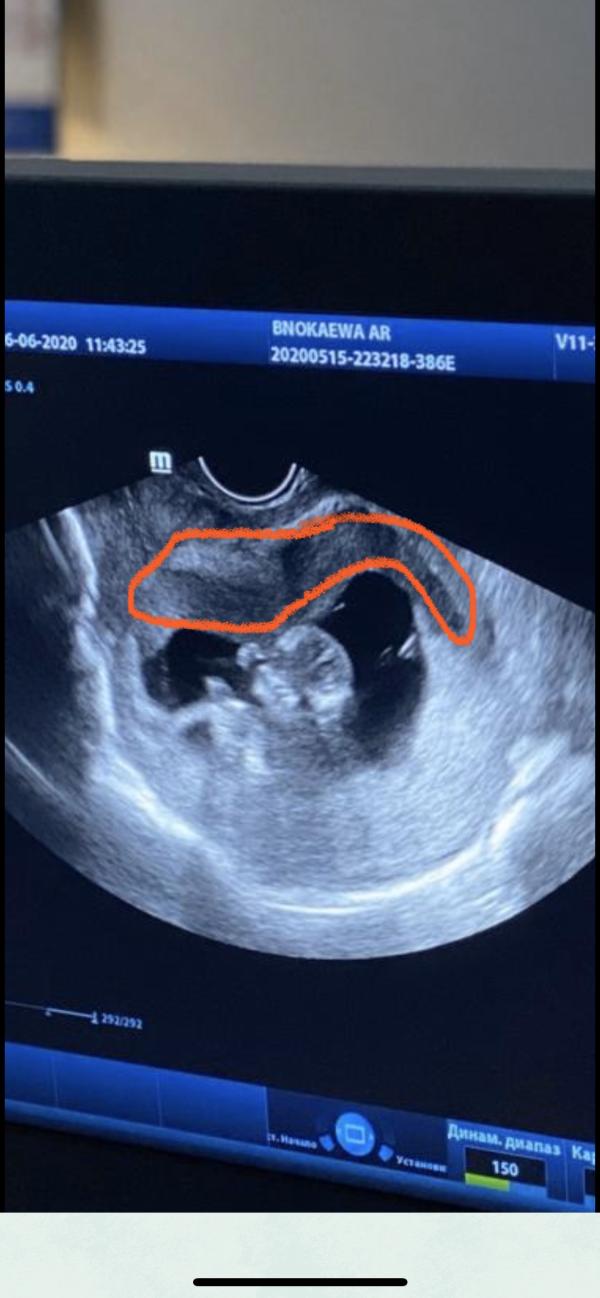

Узи показывает гематому в !4 раза больше, но как я понимаю, в другом месте. С противоположной от хориона как объяснила врач! 80х28мм и не менее 100мл крови внутри😭

Диагноз: заоболочечная гематома больших размеров.

Мне странно такое название, тк их подразделяют на ретрохориальную, субхориальную, субамниотическую. Полагаю, была врач общей практики Узи и не стала вникать. Даже не правильно гематому назвала: не заоболочная, а заоболоЧЕчная🧐

И получается на 1м узи при поступлении была субхориальная, а на 2м узи субамниотическая🤷🏼♀️